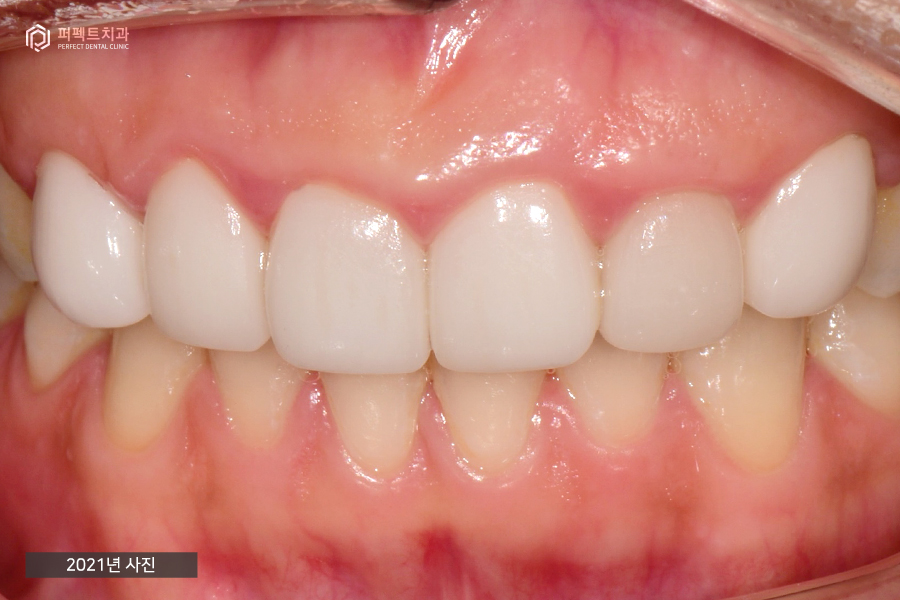

(왼)2014년 사진 / (오)2021 사진

교정 후 라미네이트로 마무리까지 한 사진입니다. 이 사진은 2014년도(왼)와 7년이 지난 2021년도(오) 사진인데 약간의 변색이 있는 치아 외에는 아주 잘 유지되고 있는 상태였습니다.

2014년도부터 지금까지 오고 계시지만 특별한 문제 없이 지내고 계시고 라미네이트가 파절되거나 교체하는 문제도 없었습니다. 이처럼 앞니에 복합적인 문제가 있더라도 치료를 받아보실 수 있으니 앞니에 문제가 있으시다면 치과를 방문하시길 바랍니다 :)